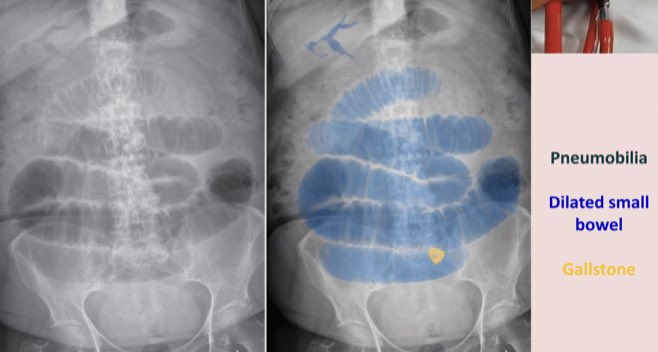

⚪️Rigler Triad ➡️ indicates cholecystoenteric Fistula with Big stone that obstruct small bowel (Gall stone ilues)

✳️Triad of:

1️⃣Pneumobilia (Air in the biliary tree 🌲)

2️⃣Small bowel obstruction Features

3️⃣Radio-Opaque Stone in the bowel (usually near the Terminal ilium)